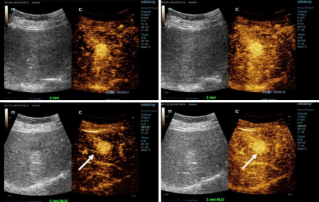

La ecografía potenciada con contraste (CEUS) es un campo muy dinámico y en los últimos años las innovaciones tecnológicas han aumentado aún más la calidad de la imagen. Una de estas innovaciones es la ecografía potenciada con contraste de alto frame-rate(HiFR CEUS), que puede generar hasta diez veces más imágenes que el ultrasonido convencional, sin demorar más tiempo.